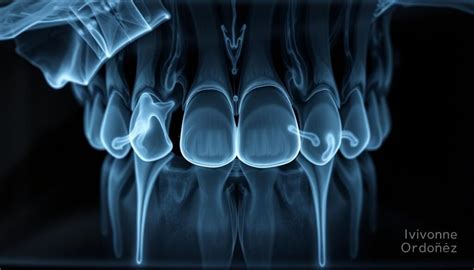

- Falta de radiografías adecuadas: No realizar radiografías para planificar la intervención puede resultar en un tratamiento incorrecto. Normalmente, se deben hacer entre cuatro a cinco radiografías en el transcurso de un tratamiento endodóntico.

Una de las herramientas más seguras y fiables para detectar una endodoncia fracasada es la radiografía dental:

- Sobreobturación: cuando el material de obturación se extiende más allá de la raíz, puede irritar los tejidos periapicales.

- Lesiones periapicales: se identifican como áreas más oscuras o radiotransparentes alrededor del ápice del diente.

- Conductos no tratados: puede que existan conductos adicionales sin tratar, los cuales aparecen como áreas radiotransparentes, ya que no han sido limpiados ni rellenados.

- Fracturas radiculares: aunque a veces son difíciles de detectar, pueden verse como líneas finas y oscuras a lo largo de la raíz.